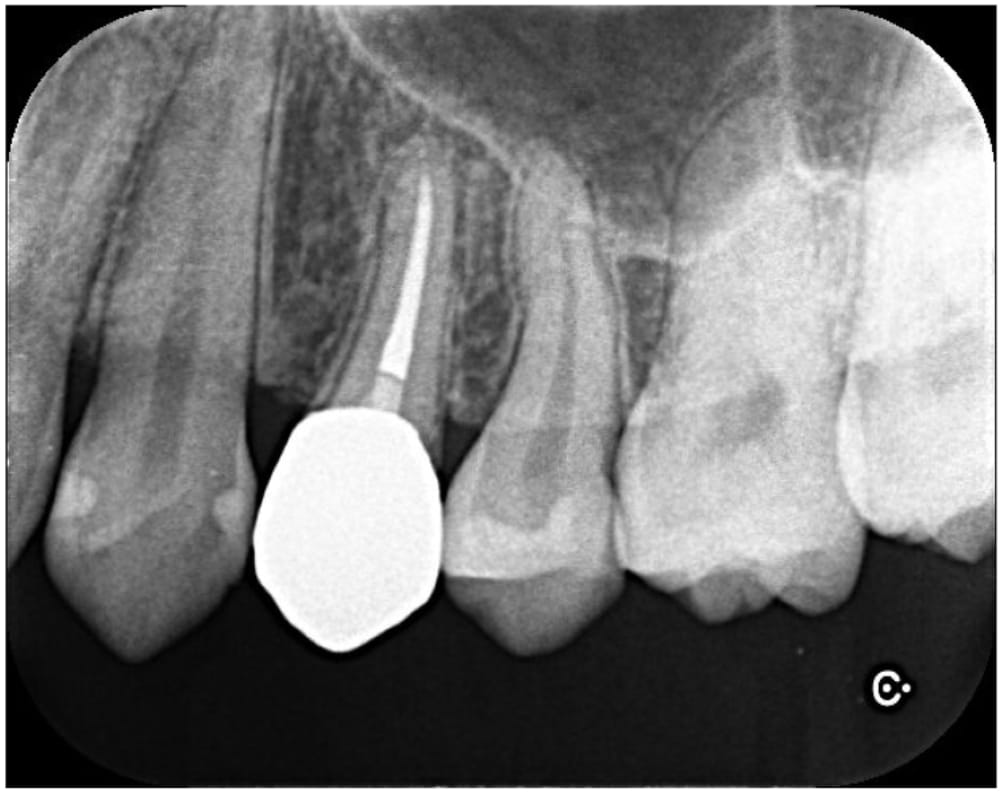

治療後6ヶ月で根尖部の透過像は縮小傾向を認め経過良好のため、ジルコニアクラウンによる最終補綴治療へ移行しました。

術後24ヶ月が経過時点でのCT画像では、もともとはっきりと写っていた根の先の黒い部分は完全に消失し、骨の回復が認められます。被せ物の適合にも問題なく、良好な経過をたどっています。